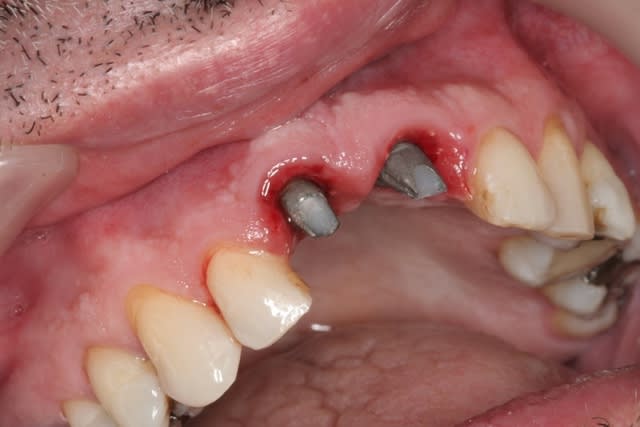

11 avec résorption interne

EII avec MCI sur du dentium (4.5/14) comblement du gap vestibulaire avec du kasios tcp (très constant dans les résultats...et très économique)

pas de photos de chir par contre...j'ai du les effacer par erreur...grrrr...

la prothèse d'usage a été réalisée par ma petite associée...mais j'étais là pour superviser et faire quelques photos...;-)